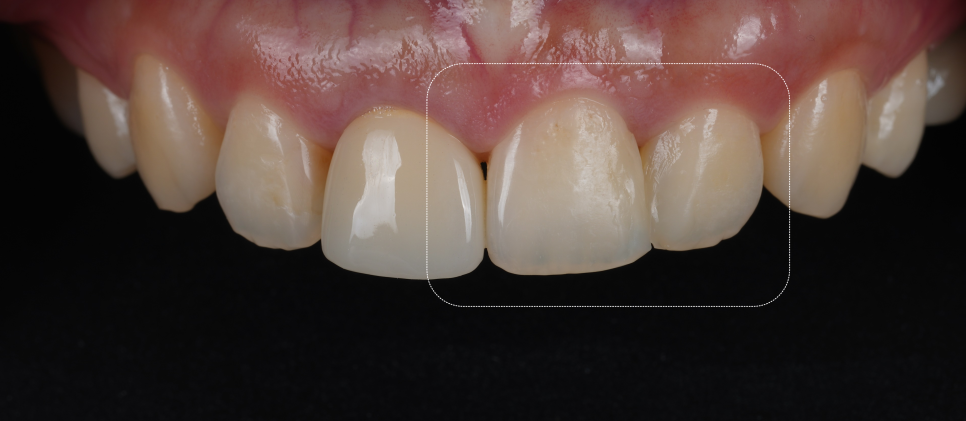

두 달 전, 다른 치과에서 앞니 사이 충치를 레진으로 메꿨는데 표면이 거칠고 빛이 반사될 때 경계가 너무 보이는 게 마음에 걸리셨대요.

또, 표면이 너무 거칠어서 계속 혀로 만지게 된다고 하시더라고요.

확인해 보니 각이져 보이는 느낌이 들었고 거칠었는데요.

촬영일 : 251023

문제는 레진의 ‘마감선’이었습니다.

서초동치과

레진과 자연치 경계가 매끄럽지 않았어요.

자연스럽게 보이려면 빛의 굴절, 반사, 곡선 등 다양한 요소들을 고려해야 하죠.

화살표를 표시해둔 곳을 잘 보시면 무슨 느낌인지 아실 거예요.

그중 어느 하나만 삐끗해도 ‘인공적인 느낌’이 나게 돼요.

이분의 경우 그 경계 하나 때문에 계속해서 신경 쓰이셨던 거죠.